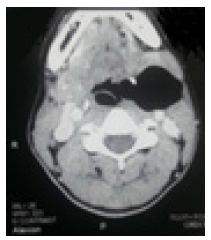

Patient 35 years old housewife admitted for mass under the angle of the left mandible found since birth. The mass has evolved in an intermittent mode with an increase in volume since about 1 year, associated with permanent dysphonia. No antecedents were noted. The mass measured about 10cm, was expansive to the Valsalva maneuver Figure 2, depressible and hinting a ‘Bryce’ sound. Nasofibroscopy revealed tumefaction of the left ventricular band. The pharyngolaryngeal computed tomography showed a circumscribed mass of air density, sitting at the level of the paraglottic region extending to the region from the angle of the left mandible Figure 3. A “J” cervical approach of Paul Andre was performed with a dissection from the laryngocele pocket to the thyrohyodial membrane Figure 4. After locating and dissecting the .superior laryngeal pedicle we proceeded to ligation and section of the laryngocele at its inlet without lateral thyrotomy. The outcome was simple with release of the patient on postoperative day 2. Anatomo-pathological examination of the operative specimen Figure 5 found a respiratory-type mucosa with a pseudostratified epithelium with hair cells and goblet cells without signs of malignancy Table 1.

Figure 3:Observation 2: pharyngolaryngeal CT showing a mixed left laryngocele.